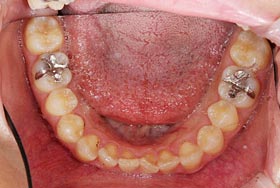

下記は、他院で虫歯と判断された患者様の症例です。

一見すると、奥歯の溝が虫歯になっているように見えます。しかし、ダイアグノデントによる診断では、虫歯治療が必要な数値を示しませんでした。つまり、歯を削る必要がないということです。